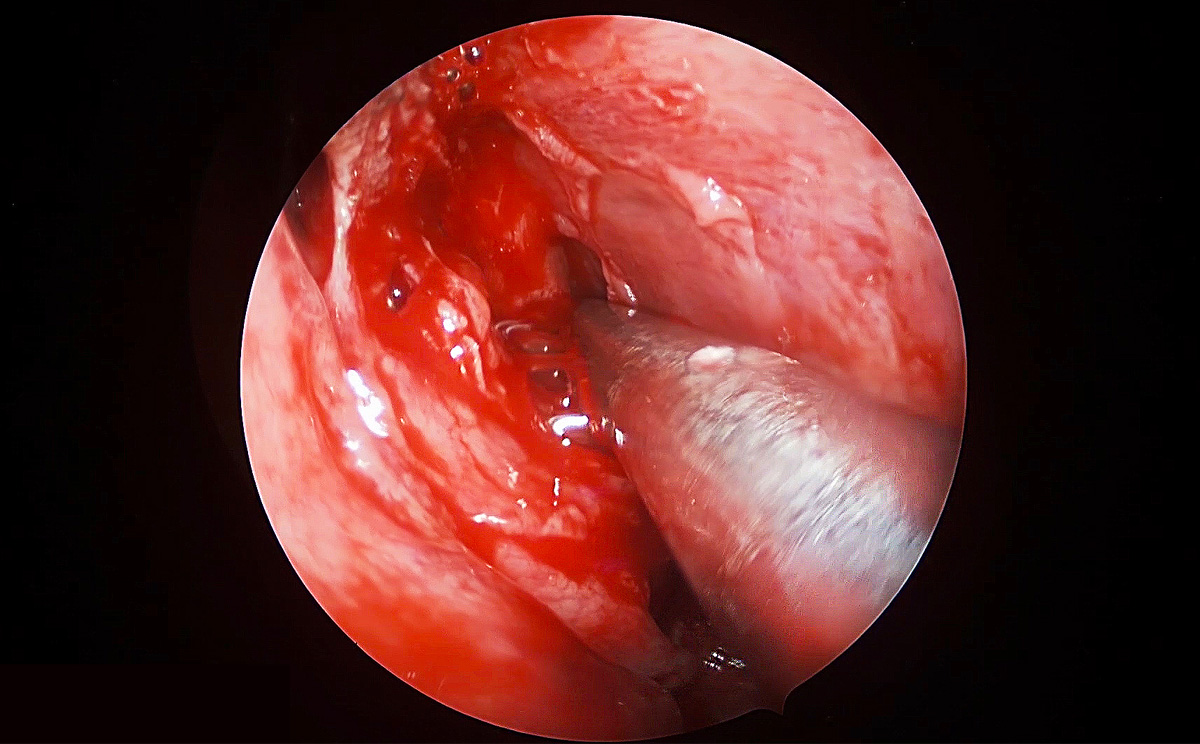

此次手術(shù)采用內(nèi)窺鏡下經(jīng)鼻進(jìn)路行腦垂體瘤切除術(shù),使用機(jī)器益柯達(dá)4K超高清內(nèi)窺鏡攝像系統(tǒng),分辨率可達(dá)3840X2160P,是全高清內(nèi)窺鏡分辨率(1920X1080P)的4倍,該產(chǎn)品具有出色的色彩還原功能,能夠精細(xì)的顯示手術(shù)中的細(xì)微血管、神經(jīng)、筋膜層次,使手術(shù)更精準(zhǔn)、安全。